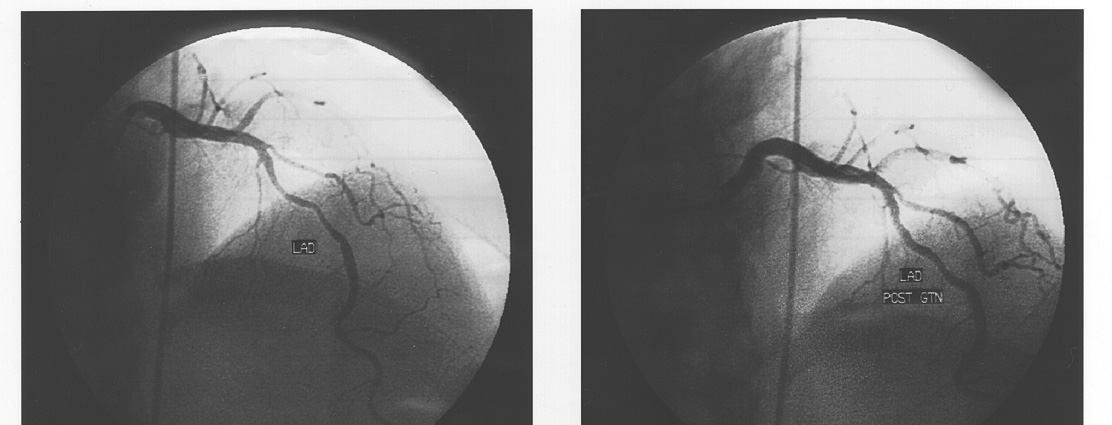

artery spasm in attacks occurring during coronary angiography (Figure 1) and

myocardial infarction associated with coronary spasm and thrombosis (Mansour,

Wilkinson, Jennings, Schwarz, Thompson & Esler, 1998).

Figure 1:

Left Panel: Coronary artery spasm in

the left anterior descending coronary

artery during a panic attack,

documented at coronary angiography.

Patient was a 51 year old woman with

unmedicated panic disorder and

anginal pain during panic attacks

Right Panel: Reversal of the spasm

with glyceryl trinitrate (GTN)